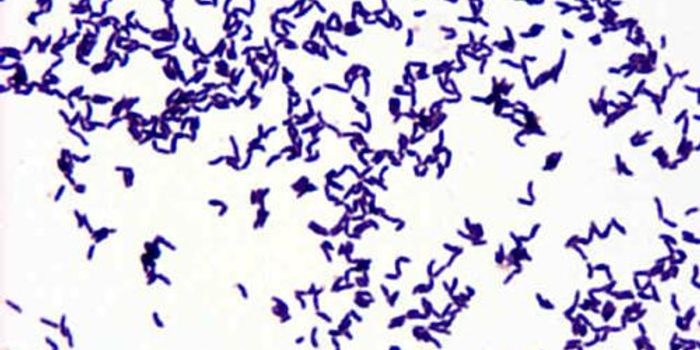

JUL 15, 2015MicrobiologyClostridium difficile is most commonly referred to as a healthcare-associated infection (HAI), with at risk-populations ...